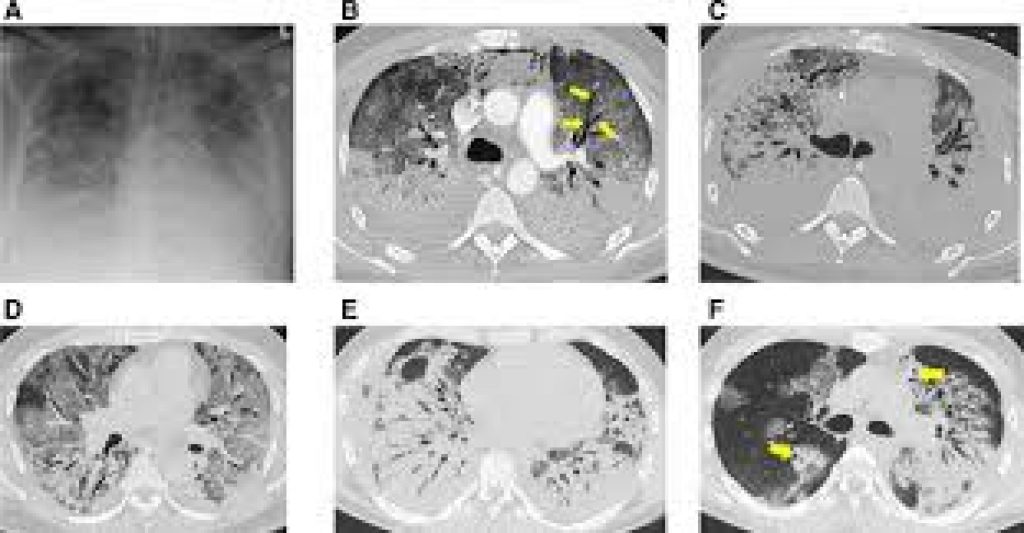

A CT scan is also known as computed tomography scan (formerly known as computed axial tomography or CAT scan).

It is a medical imaging technique used in radiology to get detailed images of the body noninvasively for diagnostic purposes.

CT scanners use a rotating x-ray tube and a row of detectors placed in the gantry to measure X-ray attenuations by different tissues inside the body.

The multiple X-ray measurements taken from different angles are then processed on a computer using reconstruction algorithms to produce tomographic (cross-sectional) images (virtual “slices”) of a body.